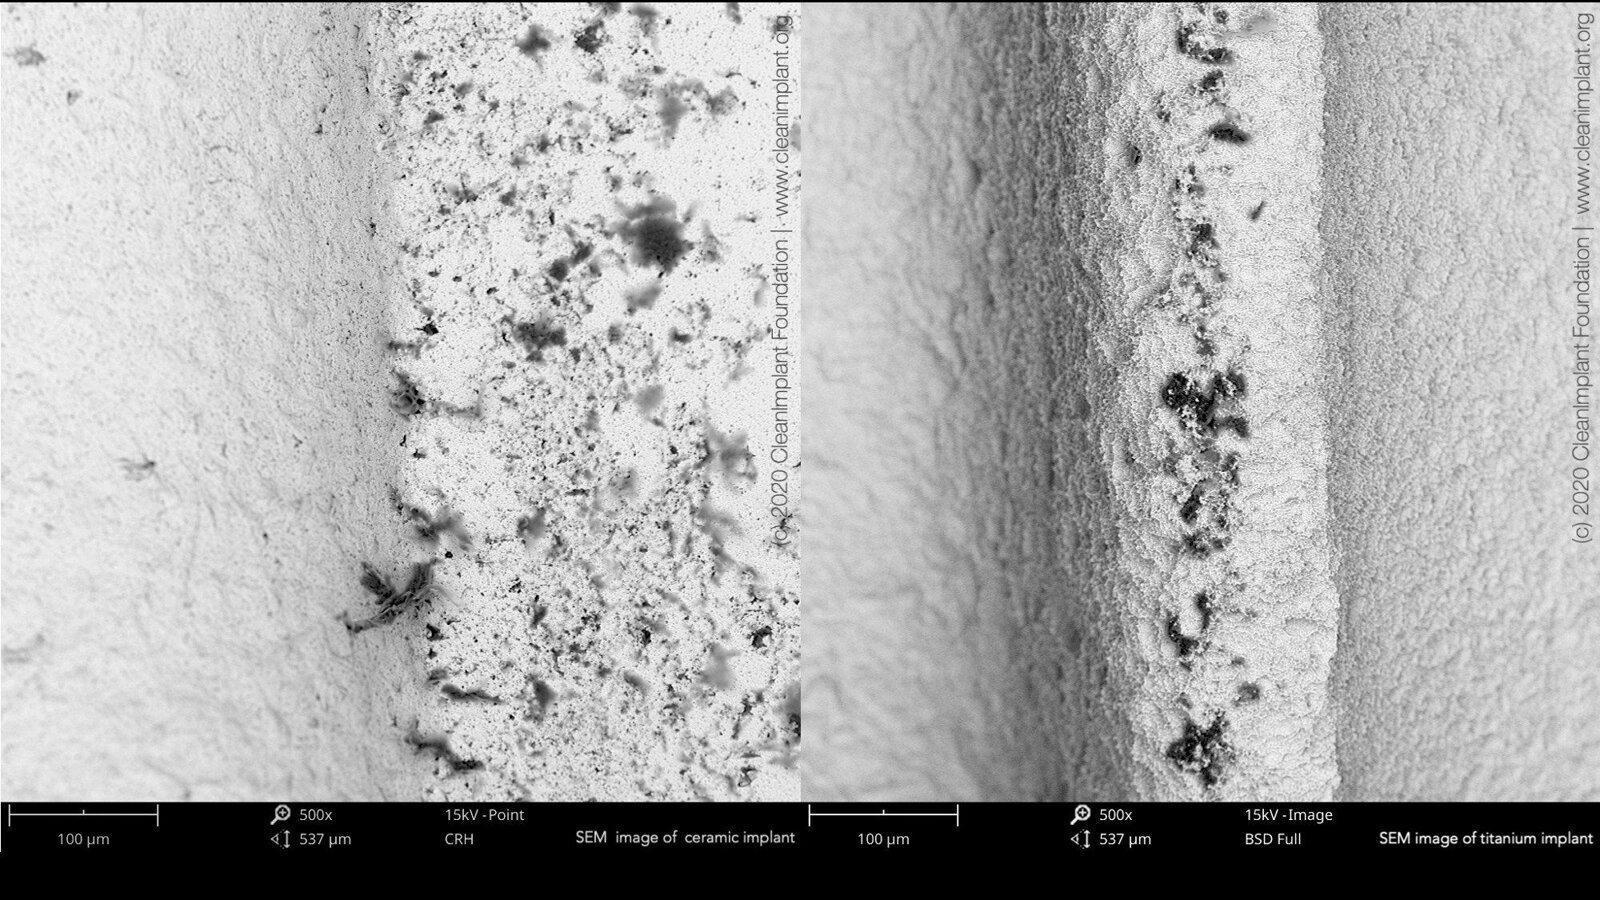

Left: Numerous organic particles (black) on a ceramic implant (SEM, 500× magnification). Right: Organic particles (black) on outer thread of titanium implant (SEM, 500× magnification). (Images: Dirk U. Duddeck)

In a recent study, conducted by the nonprofit CleanImplant Foundation in collaboration with Charité—Universitätsmedizin Berlin, Germany, more than 100 different sterile-packaged implants, including ceramic and titanium implants, from 80 implant brands were analyzed. Scanning electron microscope (SEM) imaging and elemental analysis (energy-dispersive X-ray spectroscopy) were performed in an officially accredited testing laboratory, according to DIN EN ISO/IEC 17025. Almost every second implant sample, which was unpacked under clean room conditions and analyzed under the SEM, showed considerable contamination, that is, unwanted particles originating from the manufacturing, handling or packaging of the implant. These contaminants on sterile-packaged implants, especially organic particles from the manufacturing or packaging process, can cause an uncontrolled foreign-body reaction, resulting in osteoclastogenesis and thus leaving rough areas of the implant surface exposed to bacterial colonization.1, 2 Significant amounts of foreign particles were detected on the sterile implant surfaces, not only iron, chromium, molybdenum, copper, tin, tungsten and nickel but also major organic contamination.

Additional analysis of these organic contaminants, using time-of-flight secondary ion mass spectrometry, revealed thermoplastic materials, synthetic polymers, polysiloxanes and even dodecylbenzene sulfonic acid (DBSA). DBSA is found in washing detergents and is a hazardous surfactant, according to the U.S. Environmental Protection Agency. It is noteworthy that all implants analyzed carried the FDA label or CE marking. The results showed that neither the national label for market approval nor the size or name of a manufacturer could guarantee that implant surfaces were free of significant impurities. Clinicians should think twice before considering adding zirconia implants to their portfolio just because they are white and promise to be biologically beneficial. Organic particles of 1–100 µm in diameter were also found on ceramic implant samples.